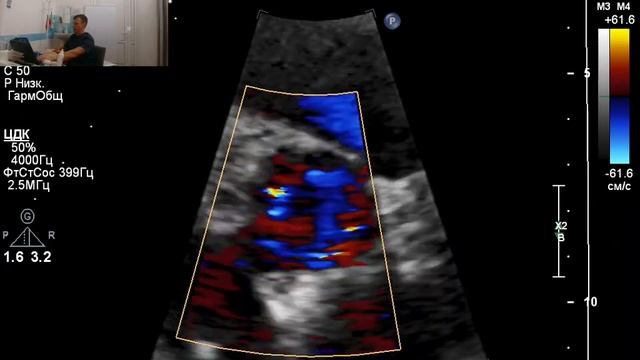

ЭХОКАРДИОСКОПИЯ (узи сердца) ребёнку в 3 месяца смотреть онлайн

Сегодня я пошла в поликлинику, чтобы сделать узи сердца своему ребёнку. Делали мне его бесплатно по направлению педиатра.